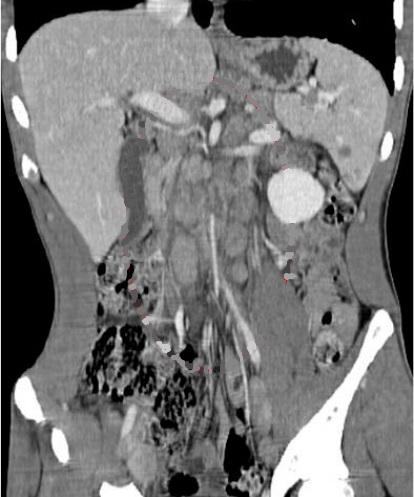

Image radiologique TDM en coupe coronal de

adenopathie peripherique , peri-splenique ,

peri-coeliacque ou mesenterique d'une lymphome maligne de la rate peu être s'observer |